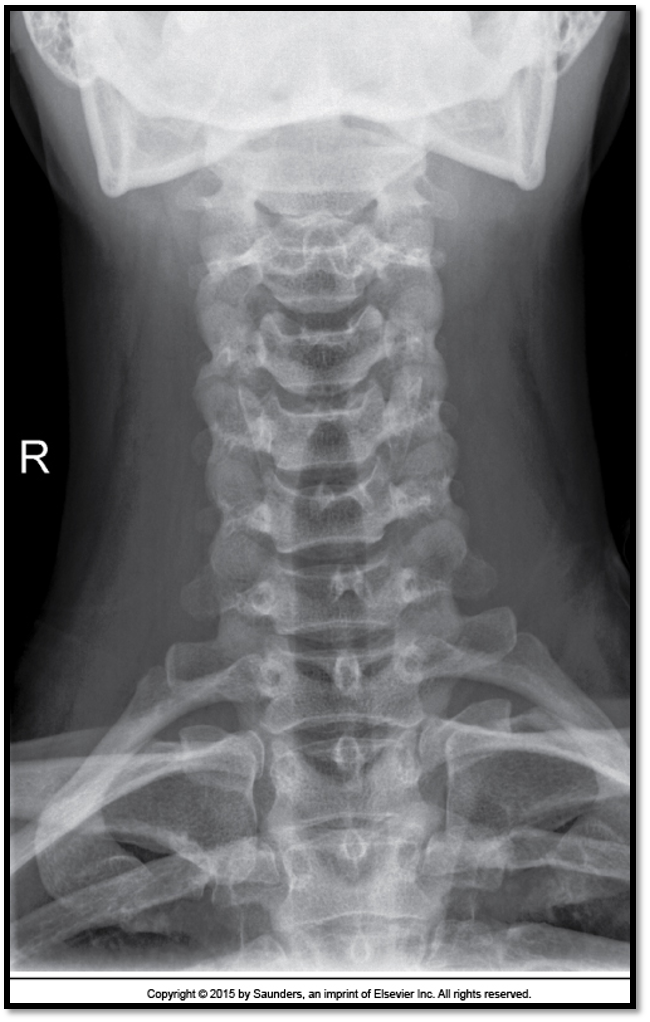

AP Axial Cspine criteria

A

• occipital bone and mandible lined up (extension)

• spinous process midline (rotation)

• open vertebral discs (angle)

• all of C3 is visible

13

Q

• need to lift the chin more

• all of C3 is demonstrated